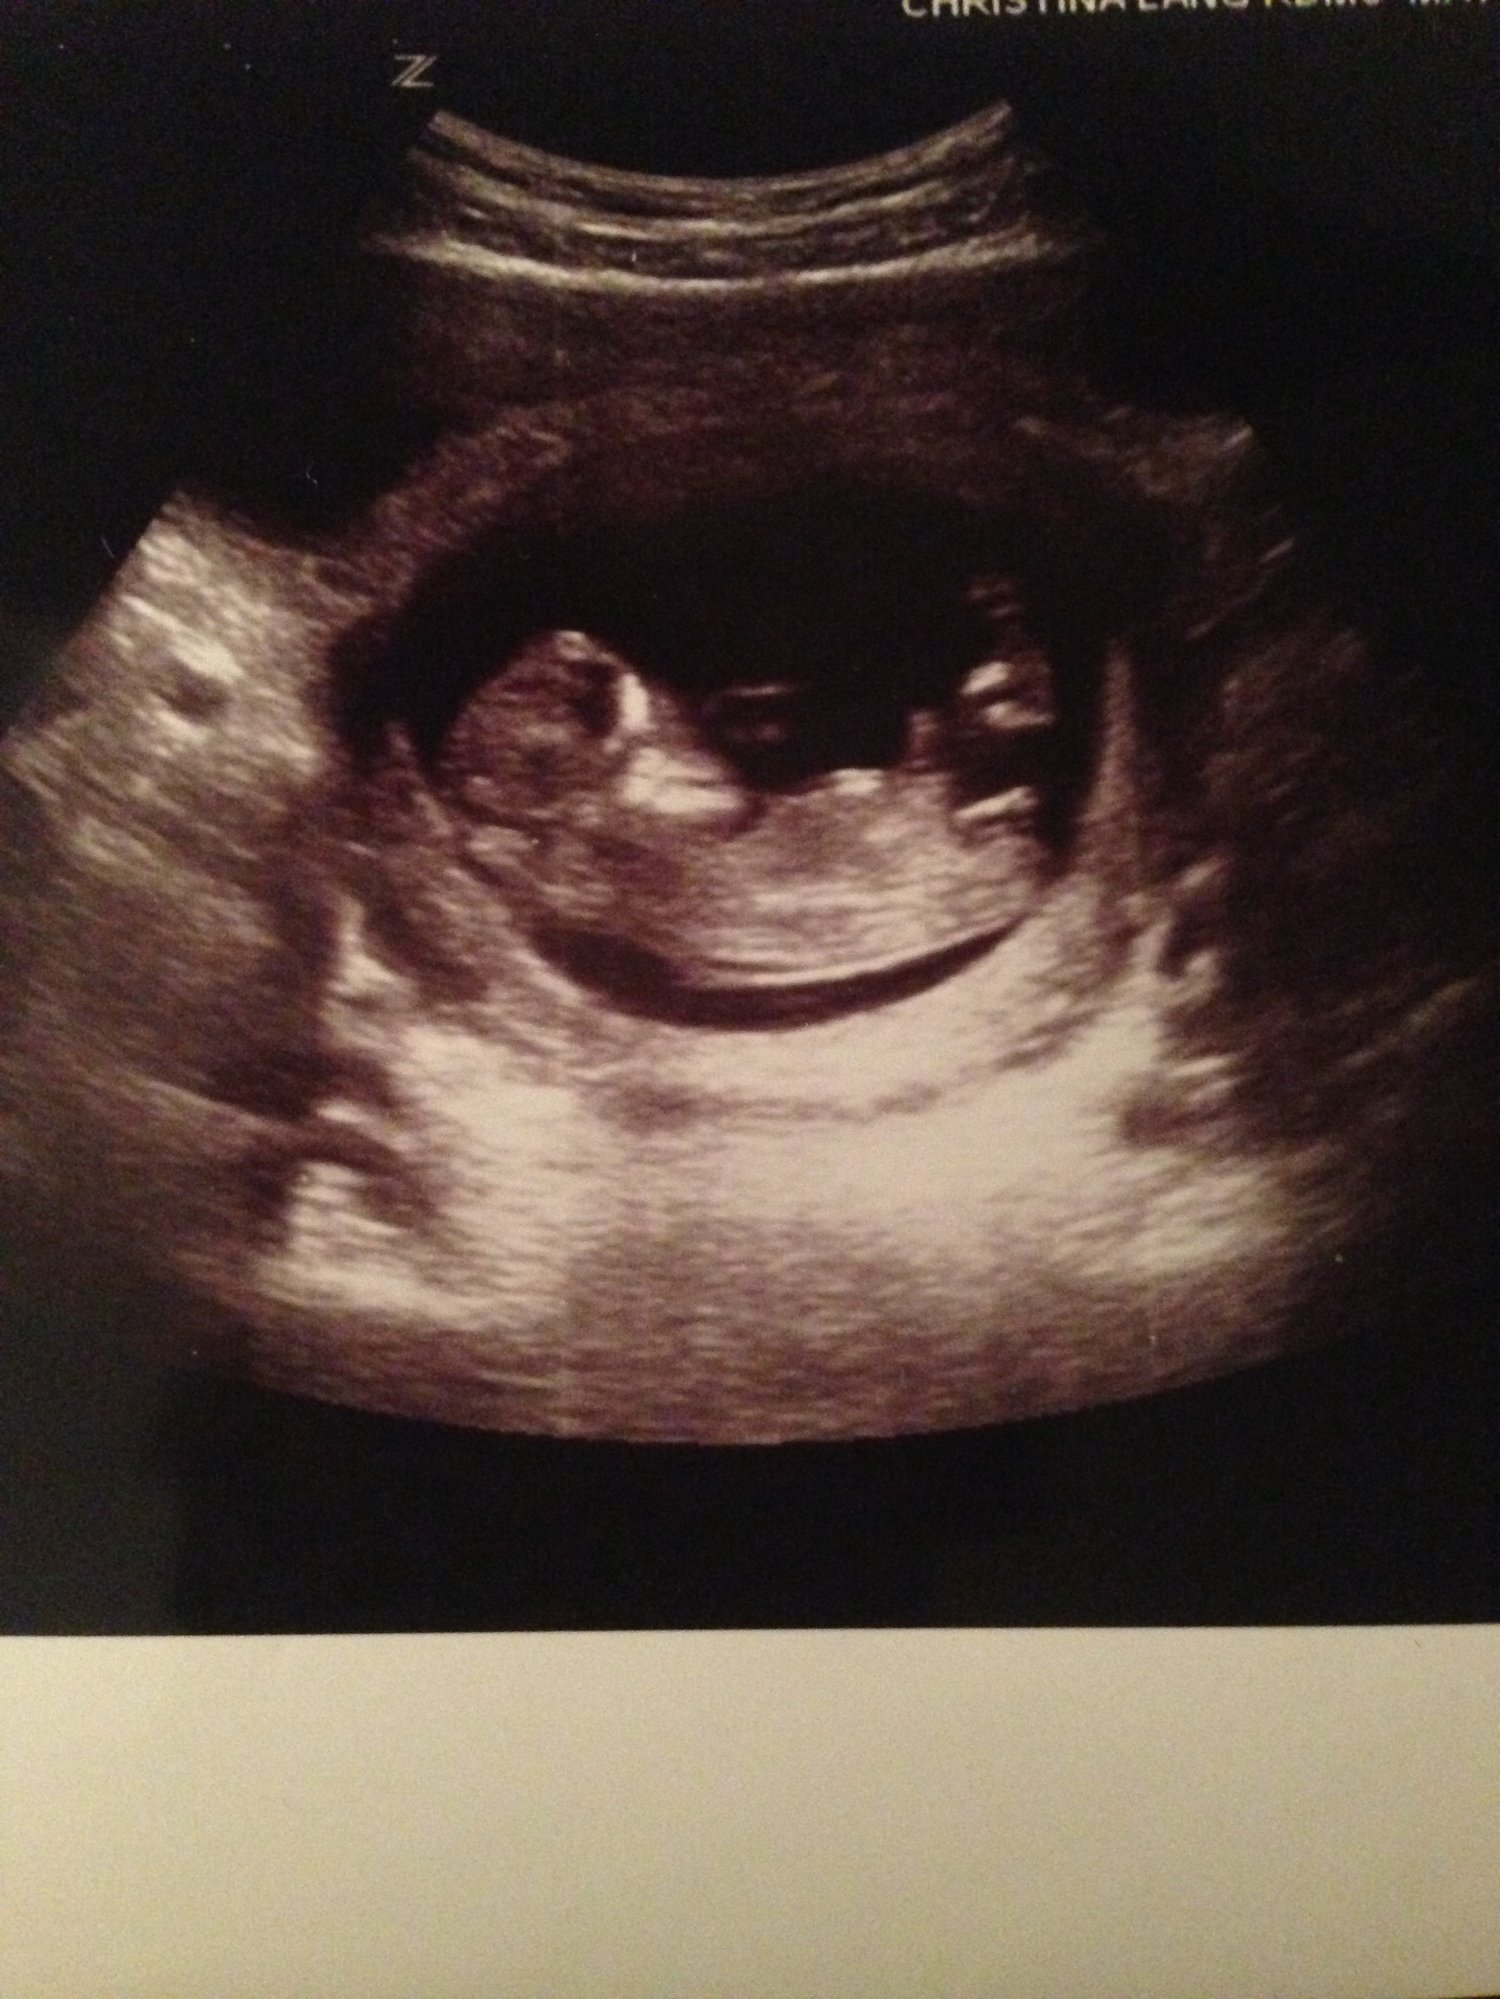

anyone familiar with the nub theory ?

any one wanna guess just for fun :)

• There's a website with a forum dedicated to nub theory guessing, even with nubs that ended up being confirmed girls or boys. I think it's called ingender.com? You'd have to google it. My guess is girl because of it being parallel to the spine and forked at the end, but nub theory isn't always right as boys can have the fork too. It's fun to guess but I wouldn't start painting the nursery just yet.

Also, only reason I made a guess is because this nub is so clearly defined. Way too many people ask for a *guess* when you can't even tell what's a nub and what's an umbilical cord/foot/anything else.

• yeah I understand I thought girl too :)

• Looks like a girl to me!

• I would say girl too.  Looks like it's parallel with the spine. This is a really clear shot, how many weeks were you? Keep us updated!

I would say girl too.  Looks like it's parallel with the spine. This is a really clear shot, how many weeks were you? Keep us updated!

I was measuring 12 weeks 2 days on the ultrasound that was june 16th I will